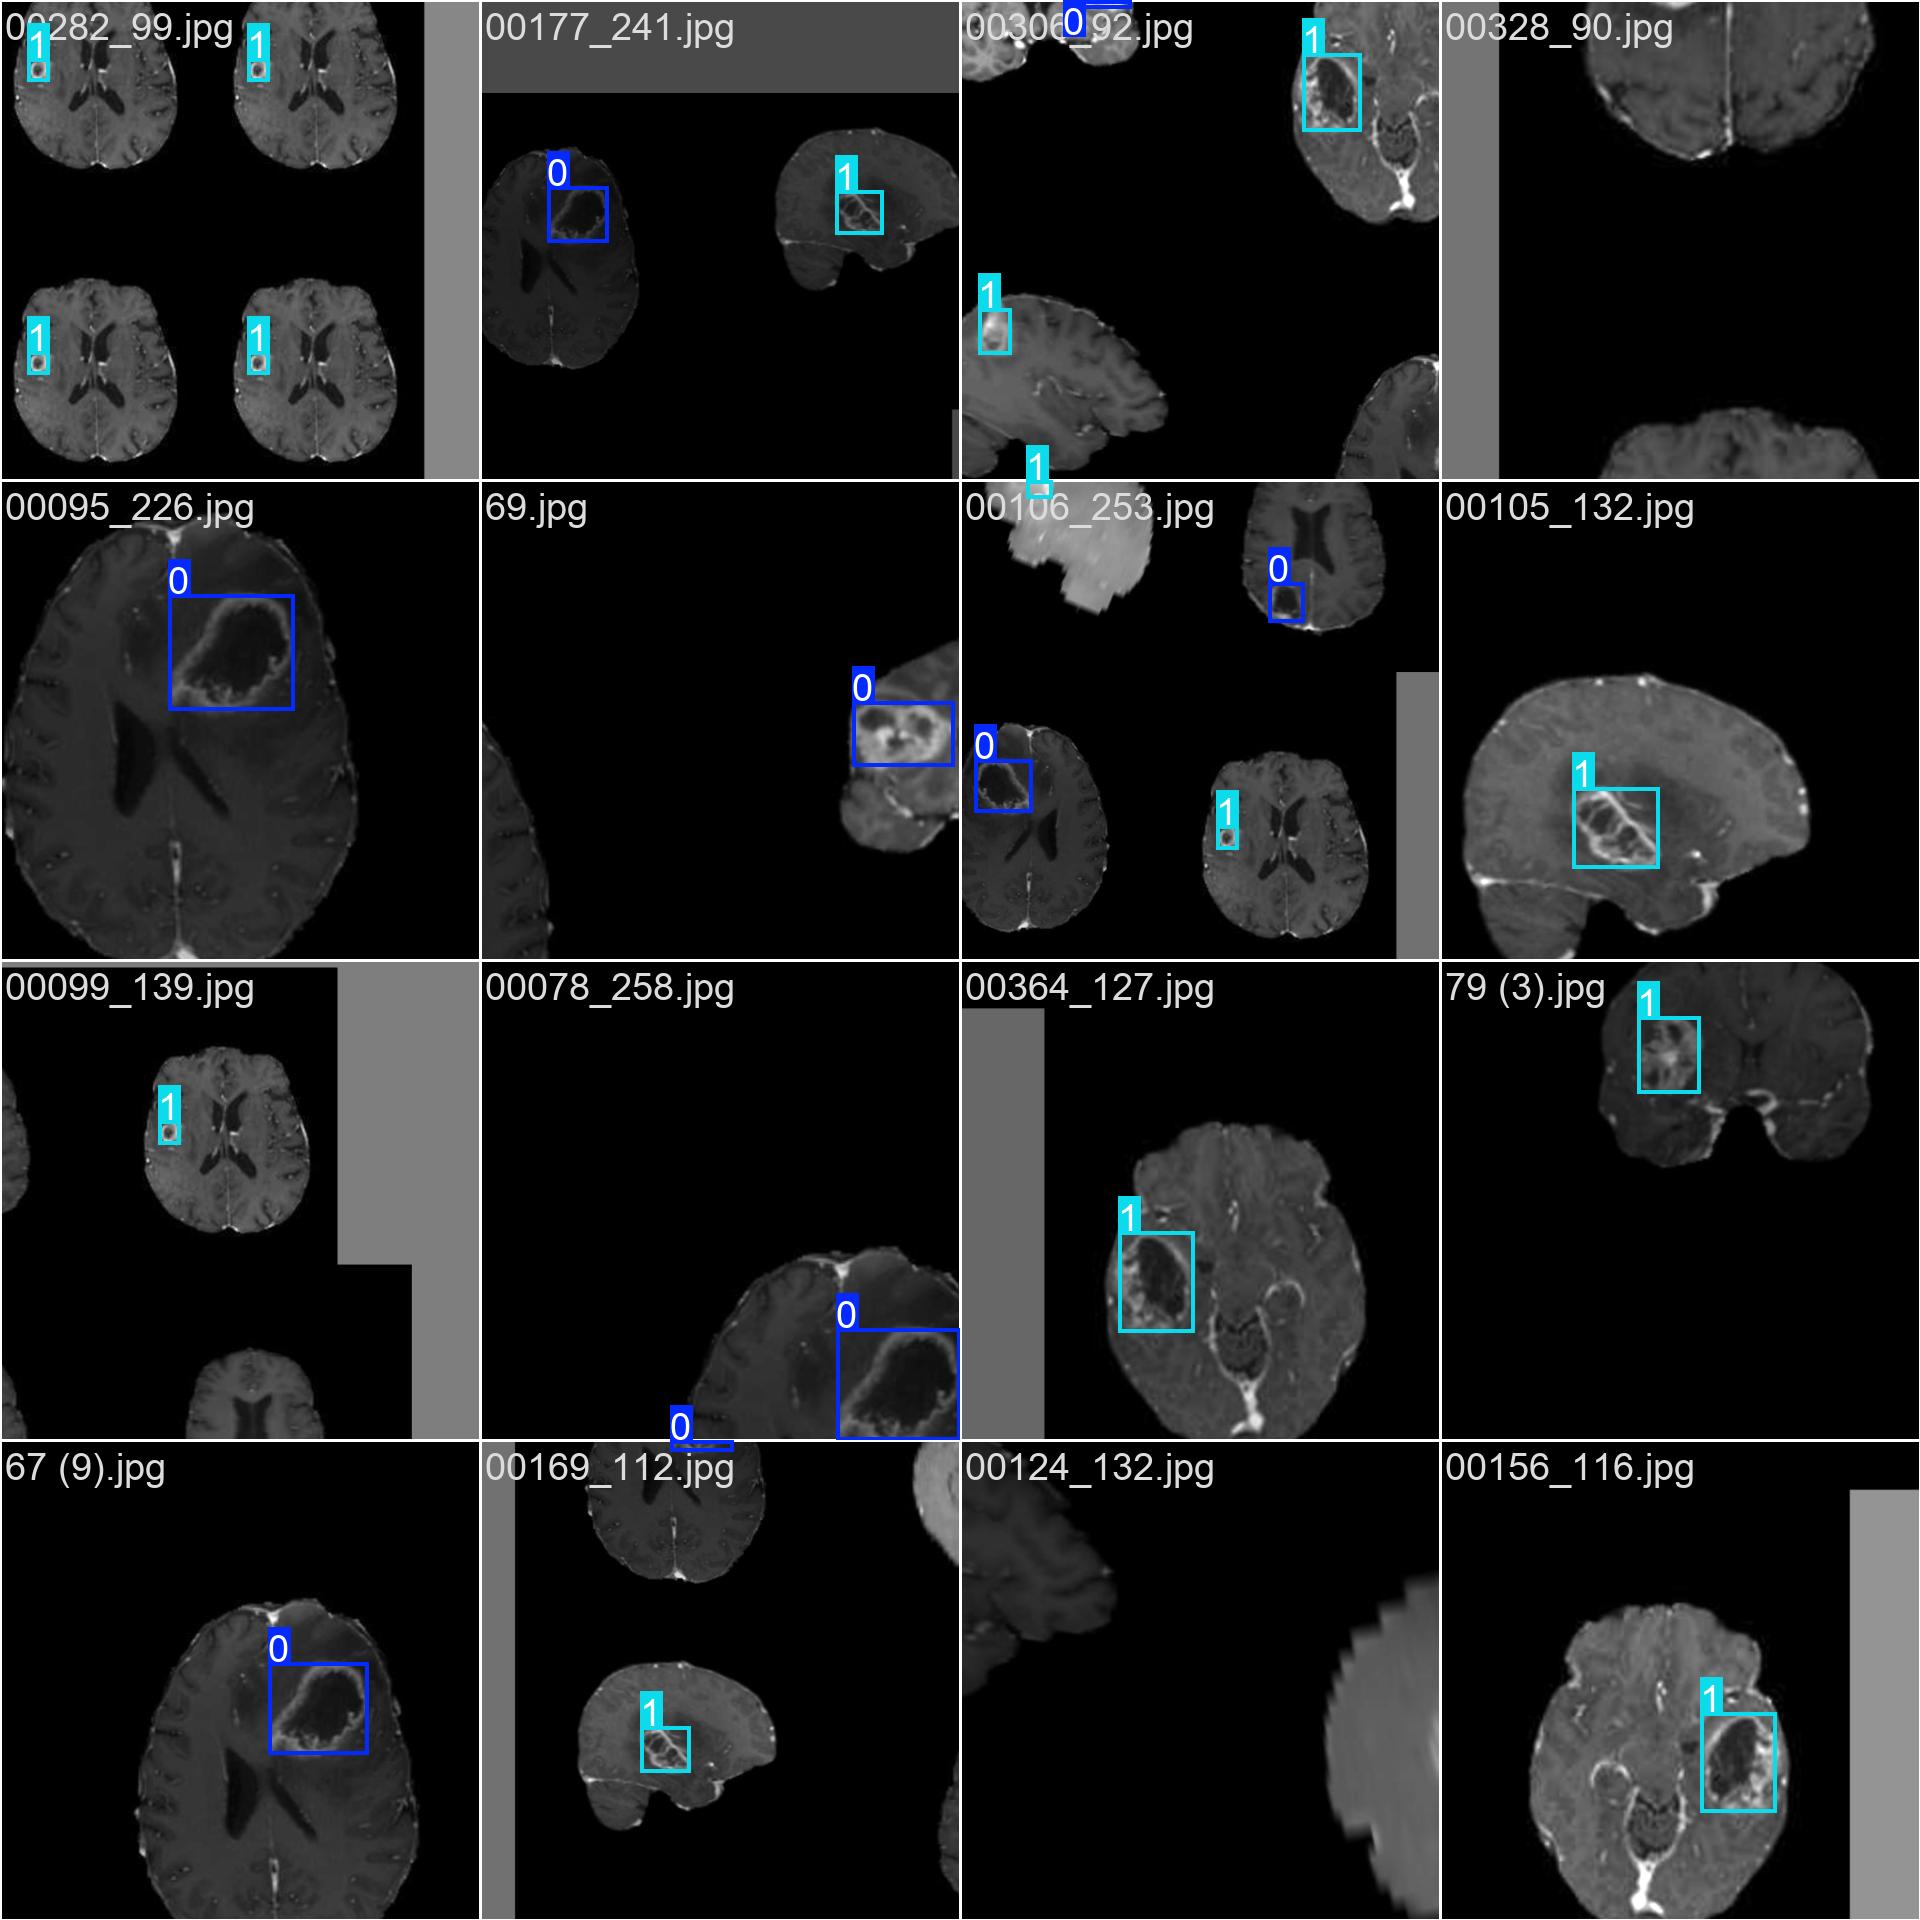

3.2 数据标注

使用标注工具(如 LabelImg, CVAT, Roboflow 等)对图像中的每一个肿瘤区域进行标注。

-

每个肿瘤需框出其边界(Bounding Box)

根据临床标准赋予类别标签:

negative或positive -

标注格式

:YOLO 使用

.txt文件存储标注信息,格式为:

txt<class_id> <x_center> <y_center> <width> <height>所有坐标值都是相对于图像宽高的归一化值(0-1)。

class_id = 0→negativeclass_id = 1→positive